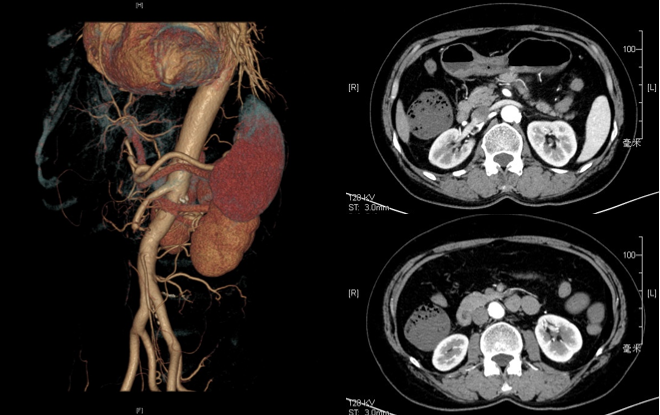

病例3:开放手术治疗

患者女性,58 岁,因 "突发腹痛 2 天" 入院,既往风心病、房颤(未规律抗凝)及颅内动脉瘤病史。查体示全腹压痛、反跳痛、肌紧张(腹膜刺激征阳性),诊断为肠系膜上动脉栓塞合并明确肠道坏死,行开腹探查 + 肠系膜动脉切开取栓 + 坏死肠道切除 + 肠道造口术,术后经营养支持及抗感染治疗,患者病情稳定出院。

图:术前影像